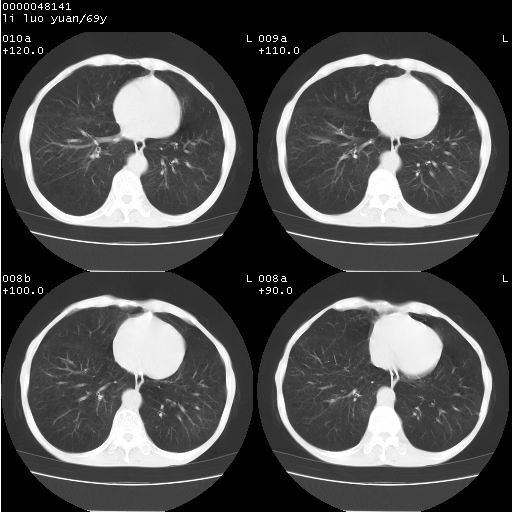

临床资料:老年患者,咯血、消瘦

影像表现:桶状胸,双肺纹理纤细、紊乱,透过度增高,肺野内可见多发、散在、大小不等的无壁高透过影,右肺中叶外侧段分叶样软组织占位,左上肺纤维索条样密度影,相应层面左侧胸腔轻度萎陷,纵隔左移。

影像诊断:1、慢支、肺气肿、双下肺野肺大泡形成

2、左上肺陈旧性肺结核

3、右肺中叶外侧段占位 考虑肺ca可能性较大、建议增强及痰检脱落细胞